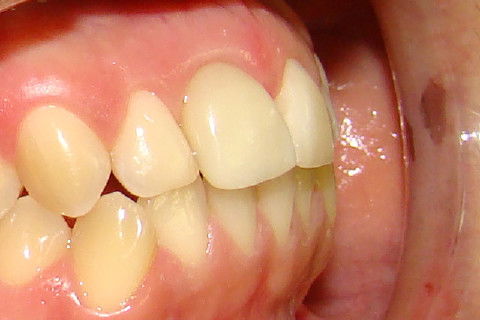

Vista da depressão gingival vestibular na região do implante a ser reaberto

Paciente com implante feito em curso de atualização, chega ao consultório para reabertura e coroa metalo-ceramica unitária, com grande depressão gengival na vestibular do elemento 11. Feita a reabertura com concomitante enxerto de tecido conjuntivo para otimizar os tecidos moles, aguardamos 3 semanas para inicio das moldagens para a coroa temporária. Após colocação e ajustes da coroa temporária parafusada, aguardamos 3 meses para completa maturação dos tecidos e então fizemos nova moldagem, com personalização do transferente para moldeira aberta individual e fizemos coros metalo-cerâmica parafusada.